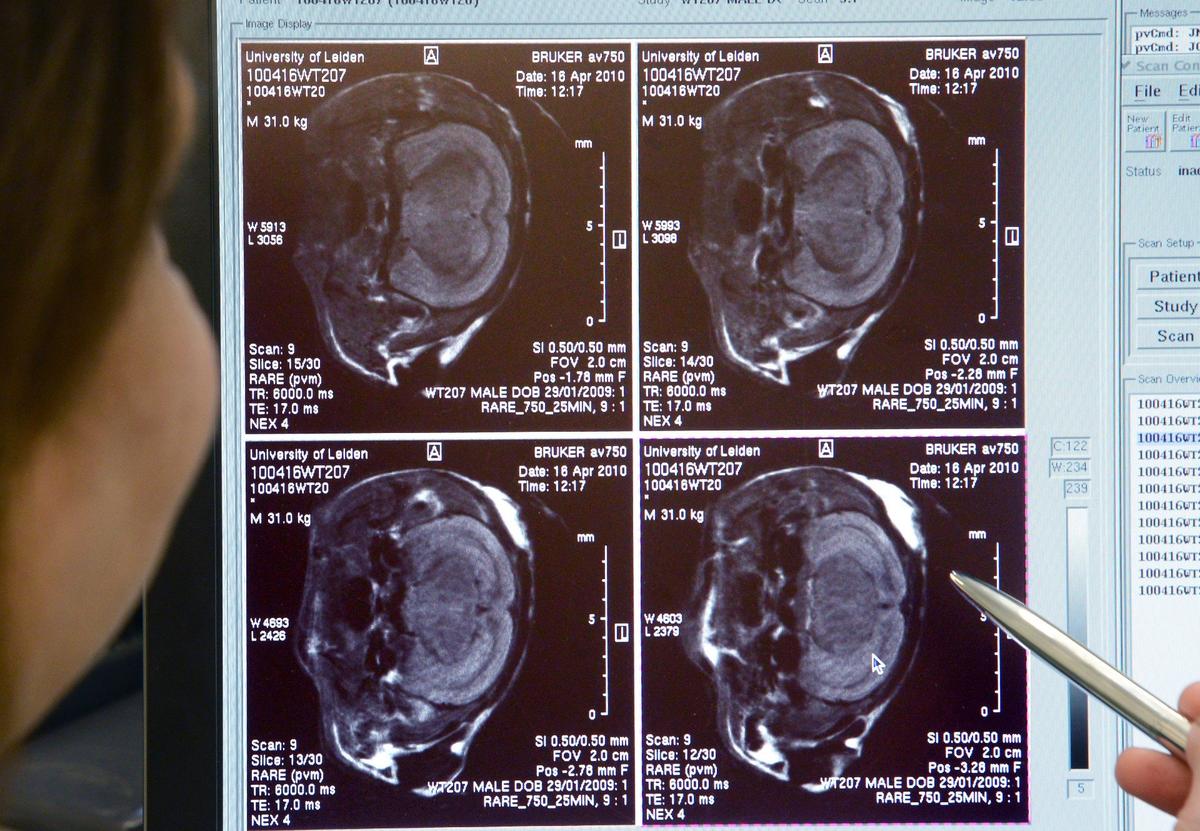

Дальше это подкрепляется данными нейровизуализации — в идеале МРТ, где мы можем видеть, что есть атрофия, то есть уменьшение в объеме преимущественно гиппокампов, если это классическая болезнь Альцгеймера, либо, например, уменьшение в объеме затылочных долей, затылочно-теменного стыка (при задней корковой атрофии).

Фото: Chen Zhongqiu / VCG / Getty Images

Но при этом применение этих антител может быть ассоциировано с развитием воспаления в месте своего действия. И это как раз то, что мы видели как нежелательные реакции на фоне адуканумаба и леканемаба: нейровизуализационные феномены, которые выявлялись при МРТ в виде отека и кровоизлияния в тех областях, где больше всего патологического бета-амилоида, включая стенки кровеносных сосудов. При этом внезапное выведение амилоида из стенки сосуда делает последнюю более хрупкой и ломкой, что создает риск развития микрокровоизлияний. А у человека нередко могут быть какие-то дополнительные факторы, предрасполагающие к кровоизлияниям: например, это артериальная гипертензия (повышение давления) или применение препаратов, которые влияют на свертываемость крови. Антиагреганты применяются очень широко, по разным показаниям (предположим, для профилактики образования тромбов на атеросклеротических бляшках), а антикоагулянты применяются либо при генетически обусловленной гиперкоагуляции, либо у людей с фибрилляцией предсердий (мерцательная аритмия), либо для профилактики образования тромбов в венах (скажем, у малоподвижных пациентов).